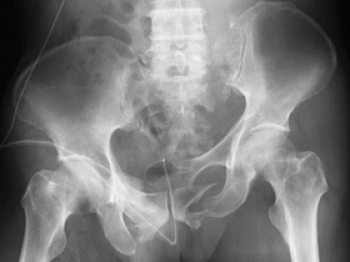

Á°²ó¡¢¹üÈ×¹üÀޤˤϡ¢¹üÈ×¹üñÆÈ¹üÀޤȹüÈ×¹ü´Ä¹üÀÞ¤¬¤¢¤ë¤³¤È¤ò¤ªÏ䵤»¤Æ¤â¤é¤¤¤Þ¤·¤¿

º£Æü¡¢¤´¾Ò²ð¤¹¤ë¤Î¤Ï¡¢¹üÈ×¹üÀÞ¤ÎʬÎà¤Î£±¤Ä¹üÈ×¹ü´Ä¹üÀޤˤĤ¤¤Æ¤´¾Ò²ð¤·¤Æ¤¤¤­¤¿¤¤¤È»×¤¤¤Þ¤¹¡£

¹üÈ×¹ü´Ä¹üÀޤȤÏ

¹üÈ×¹ü¤¬·ÁÀ®¤¹¤ë´Ä¤ÎϢ³À­¤¬¹üÀޤˤè¤Ã¤ÆÎ¥ÃǤµ¤ì¤¿¤â¤Î¤Ç¤¹¡£

¹üÀޤˤè¤Ã¤Æ¹üÈ×¹ü¤Î´Ä¤ÎϢ³¤¬Î¥ÃǤµ¤ì¤Æ¤â¡¢¤¢¤ë£±¥õ½ê¤Ç¤Î¹üÀޤξì¹ç¤ÏÈæ³ÓŪ¤Ëž°Ì¤Ï·ÚÅ٤Ǥ¹¡£

Ãѹü»Þ¤Î¹üÀÞ¤¬¡¢¹üÈ×¹ü¹üÀÞ¤¬¤â¤Ã¤È¤â¿¤¤¡£

ç¯æù¤äǢƻ¤Î¹çʻ»½ý¤¬¤ß¤é¤ì¤ë¡£

¹üÈ×Éô¤ÎÃø¤·¤¤ÊÑ·Á¤ä¡¢²¼»è¤Îû½Ì¡¡¤¬¤ß¤é¤ì¤ë¡£

¹üÈ×¹ü´Ä¹üÀÞ¤ÎʬÎà

­¡Ä²¹ü¹üÀÞ

­¢Àç¹ü¹üÀÞ

­£Ãѹü¹üÀÞ

­¤ºÁ¹ü¹üÀÞ

­¥ÀçIJ´ØÀáÎ¥³«

­¦Ãѹü·ë¹çÎ¥³«

­§¿âľ½ÅÊ£¹üÀޡʥޥ륲¡¼¥Ë¥å¹üÀÞ¡Ë

¡¡¿âľ½ÅÊ£¹üÀޡʥޥ륲¡¼¥Ë¥å¹üÀޡˤȤϡ¢Ãѹü»Þ¤äºÁ¹ü»Þ¤Î¹üÀޤˡ¢ÀçIJ´ØÀáÎ¥³«¤äIJ¹ü¸åÉô¤äÀçIJ¤¬¿âľ¤·¤Æ¹üÀÞ¤·¤¿¤â¤Î